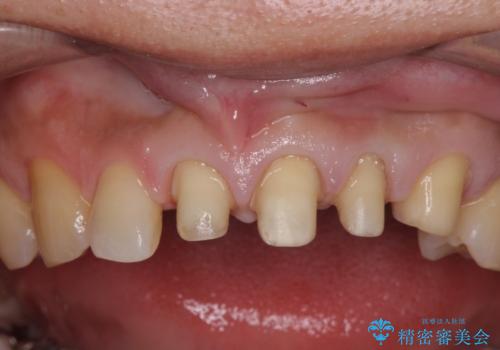

根の治療を行い、ぐらつきに関しては様子を見て連結をするとのお話をさせていただきました。

結果ナイトガードの使用によりぐらつきはだいぶ回復してきたため連結はしていません。

- 81.4万円 内訳:ジルコニアクラウン(スタンダード)11万円×4本 /精密根管治療 前歯、イニシャル 6万円×3本 /ファイバーコア 2万円×3本 /仮歯 1万円×3本/フラットタイプナイトガード 3万円費用は治療当時の料金となります